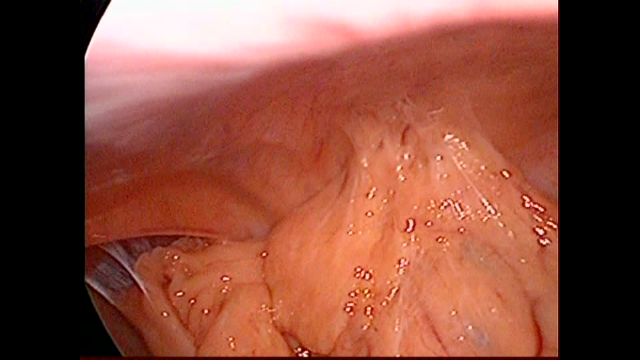

Adherencias |

Vesícula Biliar Laparoscopicas |

Esttomago Retencionista |